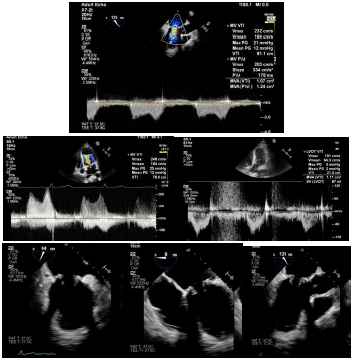

Considere um paciente de 45 anos, portador de prótese mitral biológica há 3 anos, sob anticoagulação com dispneia aos pequenos esforços. Durante o exame permaneceu com PA = 110 x 80 mmHg, em ritmo sinusal e FC = 75 bpm. Volume AE = 53 ml/m2. Área efetiva protética = 0,63 cm2/m2. Pressão sistólica da artéria pulmonar = 35 mmHg. Vmáx mitral = 2,48 m/s. VTI mitral = 78 cm, VTI VSVE = 21 cm. Gradiente AE/VE médio = 12 mmHg. PHT = 178 mseg.

AS imagens a seguir também são do paciente em tela.

Com base nos dados e traçados demonstrados nessas imagens, assinale a alternativa que apresenta a hipótese diagnóstica mais provável.